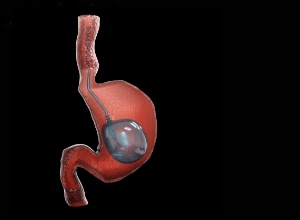

With obesity affecting 40% of the US population, the American Gastroenterological Association (AGA) has released new recommendations on the therapeutic role of intragastric balloons (IGBs), reports MedPage Today. These devices have been associated with significant improvements in weight loss over and above non-invasive standard of care (SOC) approaches.

For those for whom traditional weight loss strategies fail, IGBs have been seen to yield greater weight loss, improve metabolic laboratory abnormalities, and positively change the trajectory of several obesity-related comorbidities, the panel noted in the new clinical practice guideline.

MedPage Today reports that with respect to weight loss, IGBs led to greater weight loss at 6, 9, and 12 months after initial placement compared with patients treated with SOC alone, the document states. The amount of weight loss incrementally decreased, however, for each successive time period.

As for specific IGB type, the panel said fluid-filled balloons may promote greater weight loss but at the cost of lower tolerability and a less favourable safety profile compared with their gas-filled counterparts. Again, collaborative decision-making should be the approach in choosing a balloon device.

Obesity is a global pandemic, affecting about 40% of adults in the United States. There is a vast area of unmet need with respect to weight-loss interventions, as only 1.1% of eligible patients with obesity are receiving primary bariatric surgery. Endoscopic bariatric therapies have evolved as an attractive tool for weight loss; however, <5% of patients with obesity seeking a weight-loss therapy are aware of endoscopic weight-loss options. Intragastric balloons (IGBs) launched nearly 4 decades ago have recently gained more popularity with multiple new devices introduced into the US market. Although IGBs are a plausible option for patients seeking weight loss, it is essential for providers, patients, and health care teams to understand how IGBs can augment the effect of lifestyle modifications with respect to important patient outcome measures, such as weight loss, improving metabolic parameters, and minimizing comorbid medical conditions. At the same time, it is also important for providers and patients to be aware of the adverse events and tolerability associated with IGBs, given that the devices have evolved over the years and newer models are available in the US market. This guideline can assist both patients and providers in determining whether IGB is a weight-loss option that should be considered and/or pursued in patients with obesity.